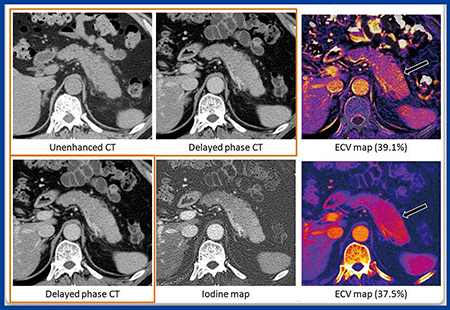

症例4(73歳,女性,自己免疫性膵炎)における通常のサブトラクション法(図6上段)のECV値は39.1%,DECT(図6下段)のECV値は37.5%であった。

図6 症例4:73歳,女性,自己免疫性膵炎